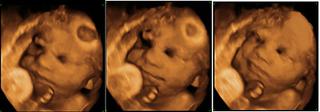

ahojte, som len na skok, vam aku velkost hlavicky namerali v tom 30TT? mne povedal ze je nejaka velka. ale tuism ju zle meral, pozdlzne, zhora sa nedalo kedze je uz dole otocene. najskor nameral 9.5 a potom nejak 8.5cm. dik za odpovede, dufam, ze sa mate dobre vsetky a vsetky ste tu stale komplet este ako kindervajicka.